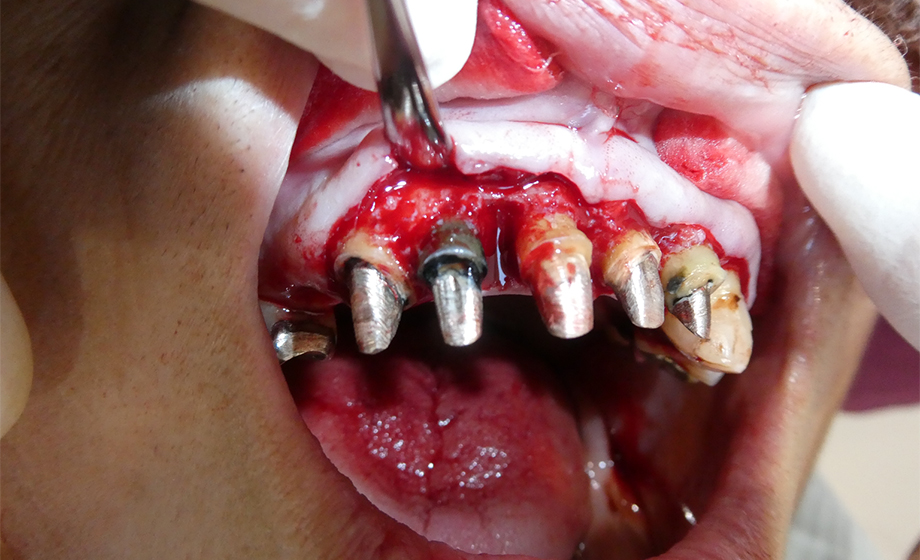

2-

術中写真

歯周外科手術中の写真です。前歯部に深い骨欠損があることがわかります。再生療法を併用して骨の回復を期待します。